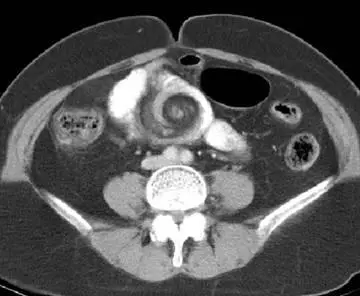

病人主訴腹脹、反胃及腹部悶痛;腹部電腦斷層檢查呈現如附圖。下列何項初診斷最恰當? 圖片描述

從提供的橫斷面CT可以觀察到:

1. 中央可見系膜血管與腸袢呈明顯螺旋狀聚集、交錯,就像天氣預報地圖上的颱風漩渦,代表腸管與系膜扭轉(whirl sign)。

2. 扭轉點近側的小腸袢明顯擴張,遠側則可見腸腔收縮,符合閉迴路小腸阻塞。

3. 無明顯典型「洋蔥圈(target)徵象」或線狀異物,亦未見闌尾肥大或周圍脂肪渲染。

上述影像特徵高度符合腸扭轉所致的旋渦徵象與閉迴路阻塞表現。

CT 的 whirl sign 為腸扭轉經典所見,扭轉點可見系膜血管與腸袢螺旋交纏,吻合小腸閉迴路阻塞與扭轉病理機轉。早期文獻指出 whirl sign 在 mesenteric volvulus 偵測上敏感且提示需儘速手術介入(pubmed.ncbi.nlm.nih.gov)。

影像中最具代表性的 whirl sign 與閉迴路阻塞特徵,明指小腸沿系膜軸扭轉,符合 mesenteric volvulus,需緊急手術減旋並評估腸管存活度。其餘選項無法解釋螺旋狀血管與腸袢扭轉的整體結構變化。正確初診斷為 volvulus。